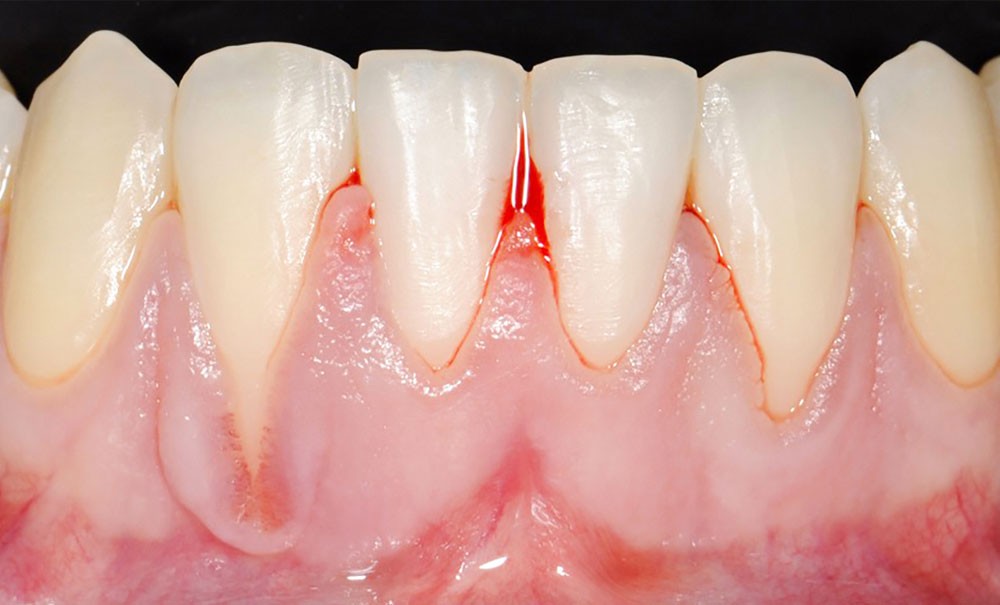

Les récessions gingivales (RG), définies comme une exposition radiculaire due à la migration apicale du rebord gingival au-delà de la jonction émail-cément, sont une situation clinique courante, rencontrée chez plus d’un adulte sur deux [1]. Le préjudice esthétique, l’hypersensibilité dentinaire ou encore la peur de perdre la (ou les) dent(s) concernée(s) sont des motifs de consultation fréquents des patients présentant des RG, en particulier les plus jeunes [2]. Les greffes gingivales sont utilisées depuis longtemps pour le traitement des RG. Une littérature abondante soutient l’efficacité de ce type de procédure pour obtenir un recouvrement radiculaire substantiel, parfois complet, et augmenter la hauteur et l’épaisseur de gencive, gage de stabilité de la position du rebord gingival [3].